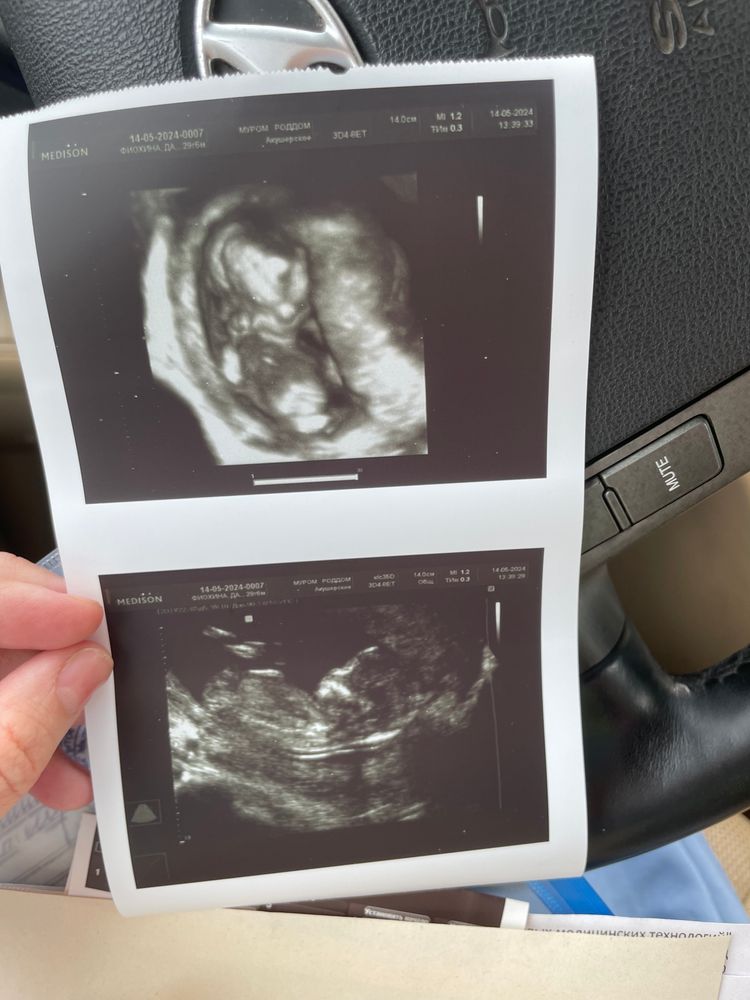

1 скрининг❤️

Поздравляю)) я сегодня тоже 1 скрининг прошла🥰 По узи все отлично, надеюсь и кровь хорошая придет😁

Дарья, нет, у нас на таком сроке не смотрят, да и к лучшему. Сходу попозже и попрошу в конверт написать, потом устроим гендер пати🤗